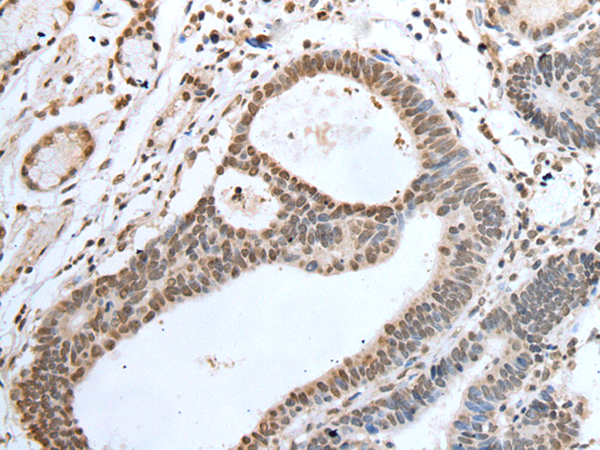

ELISA, IHC

IHC positive control:

Human lung cancer and human gastric cancer

IHC Recommend dilution: